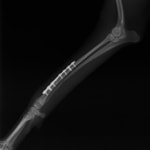

症例3:キルシュナーワイヤーのピンニングによる整復

ペルシャ猫 11ヶ月齢 雄

他院にて左大腿骨遠位の成長板骨折(salter-harrisⅠ型)が認められており、治療相談を目的として来院。当院にて、キルシュナーワイヤーを用いたピンニングにより骨折部位の整復を行いました。術後の経過は良好で、現在も経過観察中です。

術前レントゲン

術後レントゲン

Arthrex社のターゲティングデバイスを用いてピンニングの位置を調整することで、確実な固定を行っています。当院ではこの手術器具以外にも、人の手術にも使用される様々な器具を導入し、手術精度を高め、また医療メーカーと新しい器具の開発、試作にも取り組んでおります。